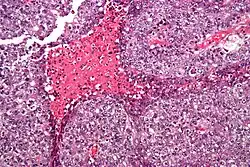

Embryonal carcinoma. H&E stain.

The gross examination usually shows a two to three centimetre pale grey, poorly defined tumour with associated haemorrhage and necrosis.[3]

The microscopic features include: indistinct cell borders, mitoses, a variable architecture (tubulopapillary, glandular, solid, embryoid bodies – ball of cells surrounded by empty space on three sides), nuclear overlap, and necrosis.